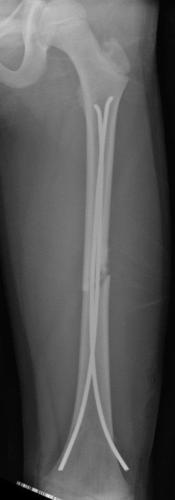

Fracture du fémur – ECMES 9 février 2024 par Damien Fracture diaphysaire du fémur G Fracture diaphysaire du fémur G : radiographie de FaceOn note un chevauchement et un déplacement en varus Fracture diaphysaire du fémur G Fracture diaphysaire du fémur G après Embrochage Centro-médullaire Elestique Stable. Radiographie post-opératoire de Face Fracture diaphysaire du fémur G Fracture diaphysaire du fémur G après Embrochage Centro-médullaire Elestique Stable. Radiographie de Face à 6 mois